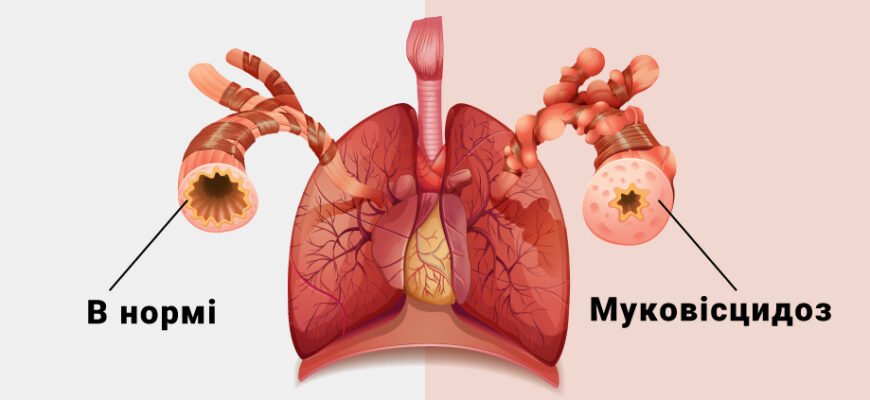

Чи можна вилікувати муковісцидоз: міф чи реальність? Муковісцидоз. Чи можна вилікувати муковісцидоз – питання, що турбує багатьох. Інколи здається, що